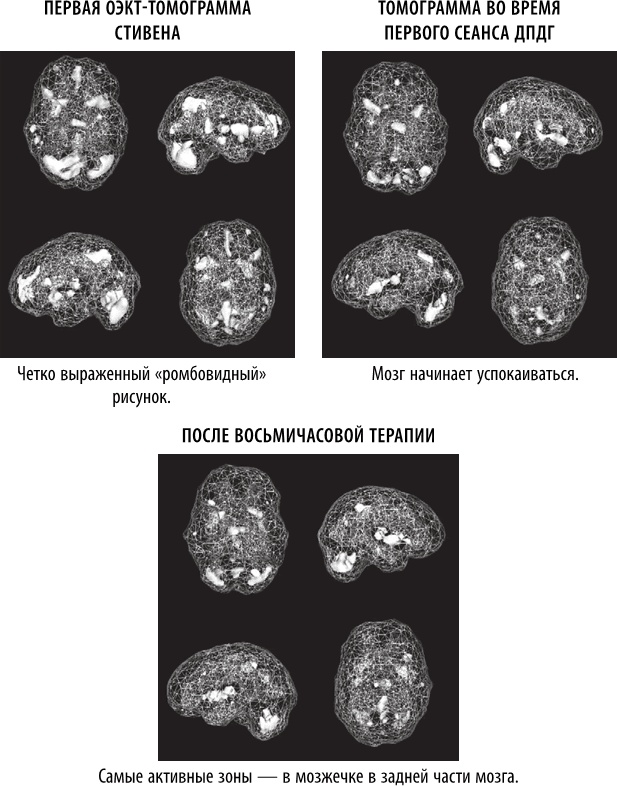

Когда продюсер CBS Анжелина Чу обратилась ко мне с вопросом, интересует ли меня телевизионный сюжет о ДПДГ с использованием истории Стивена в качестве примера, я был рад помочь. Мы с терапевтом Карен Лэнсинг только что закончили исследование о сотрудниках полиции, которые участвовали в перестрелках и в результате страдали от ПТСР [180]. Терапия ДПДГ показала свою эффективность, быстро сгладив симптомы расстройства и нормализовав мозговую функцию на ОЭКТ-томограммах. Мы с коллегами опубликовали несколько исследований о ПТСР с результатами томографии, демонстрировавшими значительный рост активности в лимбической (эмоциональной) области, образующий рисунок в форме ромба. Среди пораженных участков мозга находится передняя поясная извилина, что подразумевает фиксацию на негативных мыслях и реакциях, а также базальные ядра и миндалевидное тело, связанные с ощущением тревоги, и таламус, что указывает на повышенную сенсорную чувствительность. Кроме того, мы видели повышенную активность в правой латеральной части височной доли – области мозга, связанной с интерпретацией намерений других людей.

Иллюстрация к книге — Полюби свой мозг [i_027.jpg]

В ходе эксперимента мы трижды просканировали мозг Стивена: до терапии, во время первого сеанса ДПДГ и после восьми часов лечения. Сначала мозг Стивена демонстрировал классические симптомы ПТСР с крайне высокой активностью лимбической (эмоциональной) системы мозга. С помощью ДПДГ мы начали поочередно «очищать» психические травмы. Уже после первого сеанса появились признаки улучшения, а после восьми часов терапии (см. изображения выше) общая картина значительно улучшилась. У Стивена прекратилась неконтролируемая дрожь, он стал более спокойным и менее напряженным. Одним из самых поразительных эффектов терапии, которым Стивен поделился со мной, было то, что он постепенно начал прощать своего отца и думать о том, как выглядел отцовский мозг. Стивен питал глубокое и понятное отвращение к отцу, но нейронаука позволила ему посмотреть на себя и своего отца с новой стороны. Когда мы помогли Стивену успокоить и уравновесить его мозг, он стал более жизнерадостным человеком и смог лучше спать.